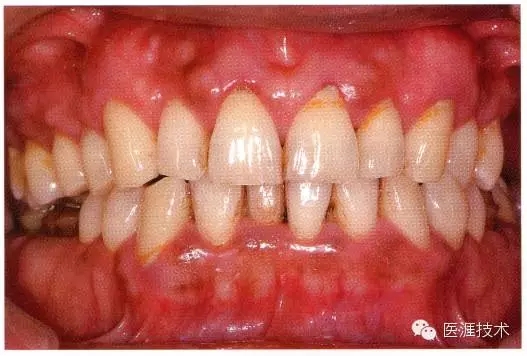

患牙齦炎時(shí)牙齦腫脹并發(fā)紅。一般從牙間乳頭部開始擴(kuò)大到牙齦邊緣。齦溝滲出液增加,受刷牙等刺激容易出血。游離齦溝、step ring消失形成假性牙周袋,纖維性肥厚呈帶狀。下顎前牙舌側(cè)及上顎臼齒臉頰側(cè)等唾液腺開口部附近還可見發(fā)白的齦上牙石。

患牙齦炎如采取適當(dāng)治療是可以恢復(fù)到原來的狀態(tài)的。

患牙齦炎的牙周組織的臨床圖像

22歲男性牙齦炎的臨床圖像

22歲男性,抽煙(1天約15根,煙齡5年)。刷牙狀態(tài)不佳。抽煙者特有的纖維性牙齦,未見發(fā)紅、腫脹。探針觸診,所有部位均出血。X線牙片未見骨吸收,診斷為牙齦炎。

14歲男性牙齦炎的臨床圖像

14歲男性。刷牙狀態(tài)不佳。整顎浮腫性發(fā)紅、腫脹且刺激出血。牙頸部有早期齲(白斑)。

26歲男性牙齦炎的臨床圖像

26歲男性。開口呼吸?;旌嫌醒例l發(fā)紅、腫脹與纖維性肥厚。菌斑干燥牢牢黏住,刷牙難以刷掉。